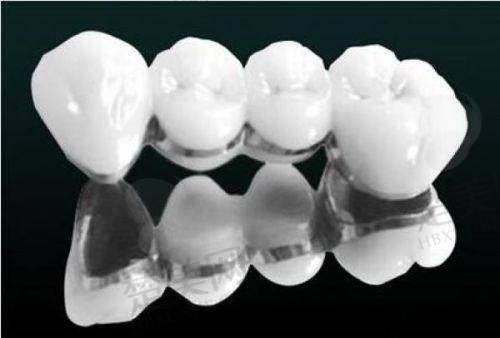

种植牙项目是该门诊部的一大特色。它支持多种种植牙技术,如all - on - 4种植、穿颧穿翼技术、微创即刻种植、all - on - 4即刻负重等。采用数字化3D诊疗设备,医生可以更精细地了解患者牙槽骨的情况,为患者制定更合适的种植方案。在种植过程中,医生经验多,像陈东斌医生擅长口腔颌面外科牙槽骨各类复杂种植外科手术,陈牙斌医生擅长普通种植牙、高难度的all - on - 4种植技术、穿颧穿翼种植。这些医生能够熟练操作各种种植技术,确保种植手术的顺利进行。而且,门诊部使用的种植牙品牌多样,有韩国奥齿泰、瑞士士卓曼ITI、德国HT、瑞士诺贝尔nobel等,患者可以根据自己的需求和经济状况进行选择。

龙岩雅致口腔门诊部纳米树脂补牙约300元/颗。牙齿矫正方面,不同的矫正方式价格有所不同,自锁托槽矫正、隐形矫正等价格需根据患者具体情况确定。种植牙的价格因品牌和种植技术而异,韩国奥齿泰、瑞士士卓曼ITI等不同品牌价格有别。牙齿美白、牙冠修复等项目的价格也会因材料和具体治疗方案而有所不同。